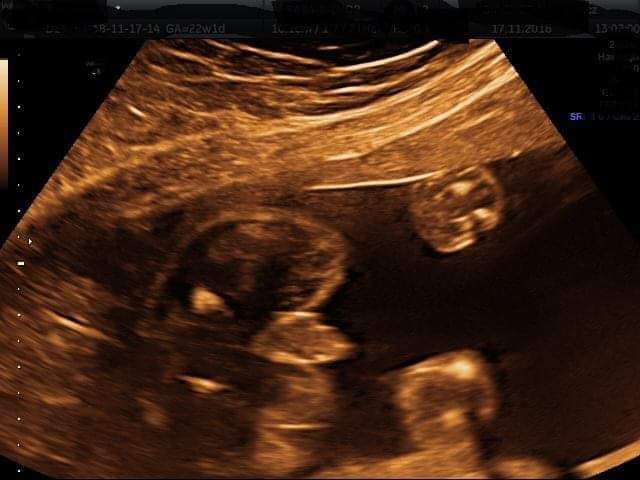

Witam w 19 tygodniu ciąży dowiedziałam się ze będę miała dziewczynkę w 20 tyg okazało się jednak , że to chłopak. Sama już nie wiem bo na jednym usg widać na pewno dziewuche a na drugim chłopca. Może to pempowina ?? Może ktoś mi pomoże rozwiązać ta zagadkę

Załączniki

• 4A8F5FF1-76CA-4DE0-AC12-5EDF08E820F2.jpg

4A8F5FF1-76CA-4DE0-AC12-5EDF08E820F2.jpg

596,4 KB · Wyświetleń: 43 679